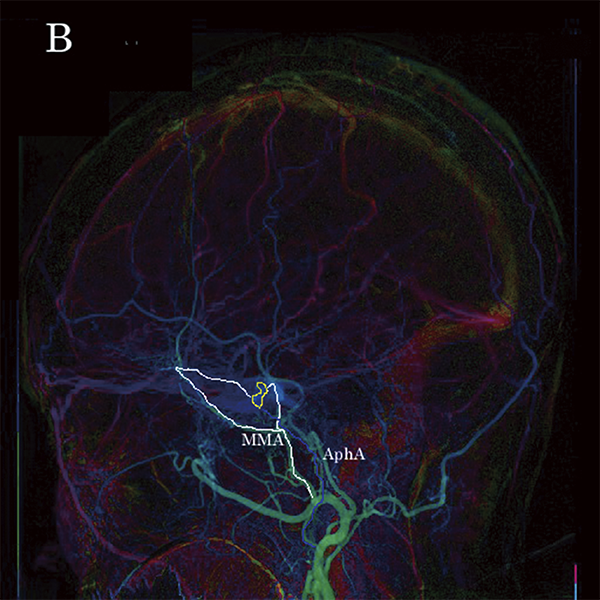

Новий параметричний метод кольорового кодування зображення (Color Coded Circulation, CCC) (малюнок 10A та 10B) дозволяє спостерігати за змінами кольору на динамічному зображенні, що полегшує розуміння напрямку кровотоку. Зображення CCC можуть бути створені автоматично, після DSA, що дозволяє спостерігати за змінами кровотоку під час процедури. У цьому випадку передопераційна DSA чітко продемонструвала ретроградний потік до поверхневої середньої мозкової вени (SMCV) та мішечок, у якому сходилися точки шунтів, що було підтверджено CCC (малюнок 10A та 10B, жовта ROI). Фідер був націлений з лівого кавернозного синуса (CS) і висхідної глоткової артерії (AphA). Фідер на лівій середній менінгеальній артерії (ММА) заклали спіралями. AphA емболізували, а потім через нижній кавернозний синус (ICS) емболізували ділянку від лівого CS до місця злиття з правим CS. Процедуру було завершено після підтвердження антеградного кровотоку у верхній очній вені (SOV) і SMCV.

Малюнок 10A: ССС зображення CSdAVF (вид спереду). Жовта досліджувана ділянка: сумка, біла лінія: MMA – фідер

Малюнок 10B: ССС зображення CSdAVF (вид збоку). Жовта досліджувана ділянка: сумка для шунта, біла лінія: MMA – фідер